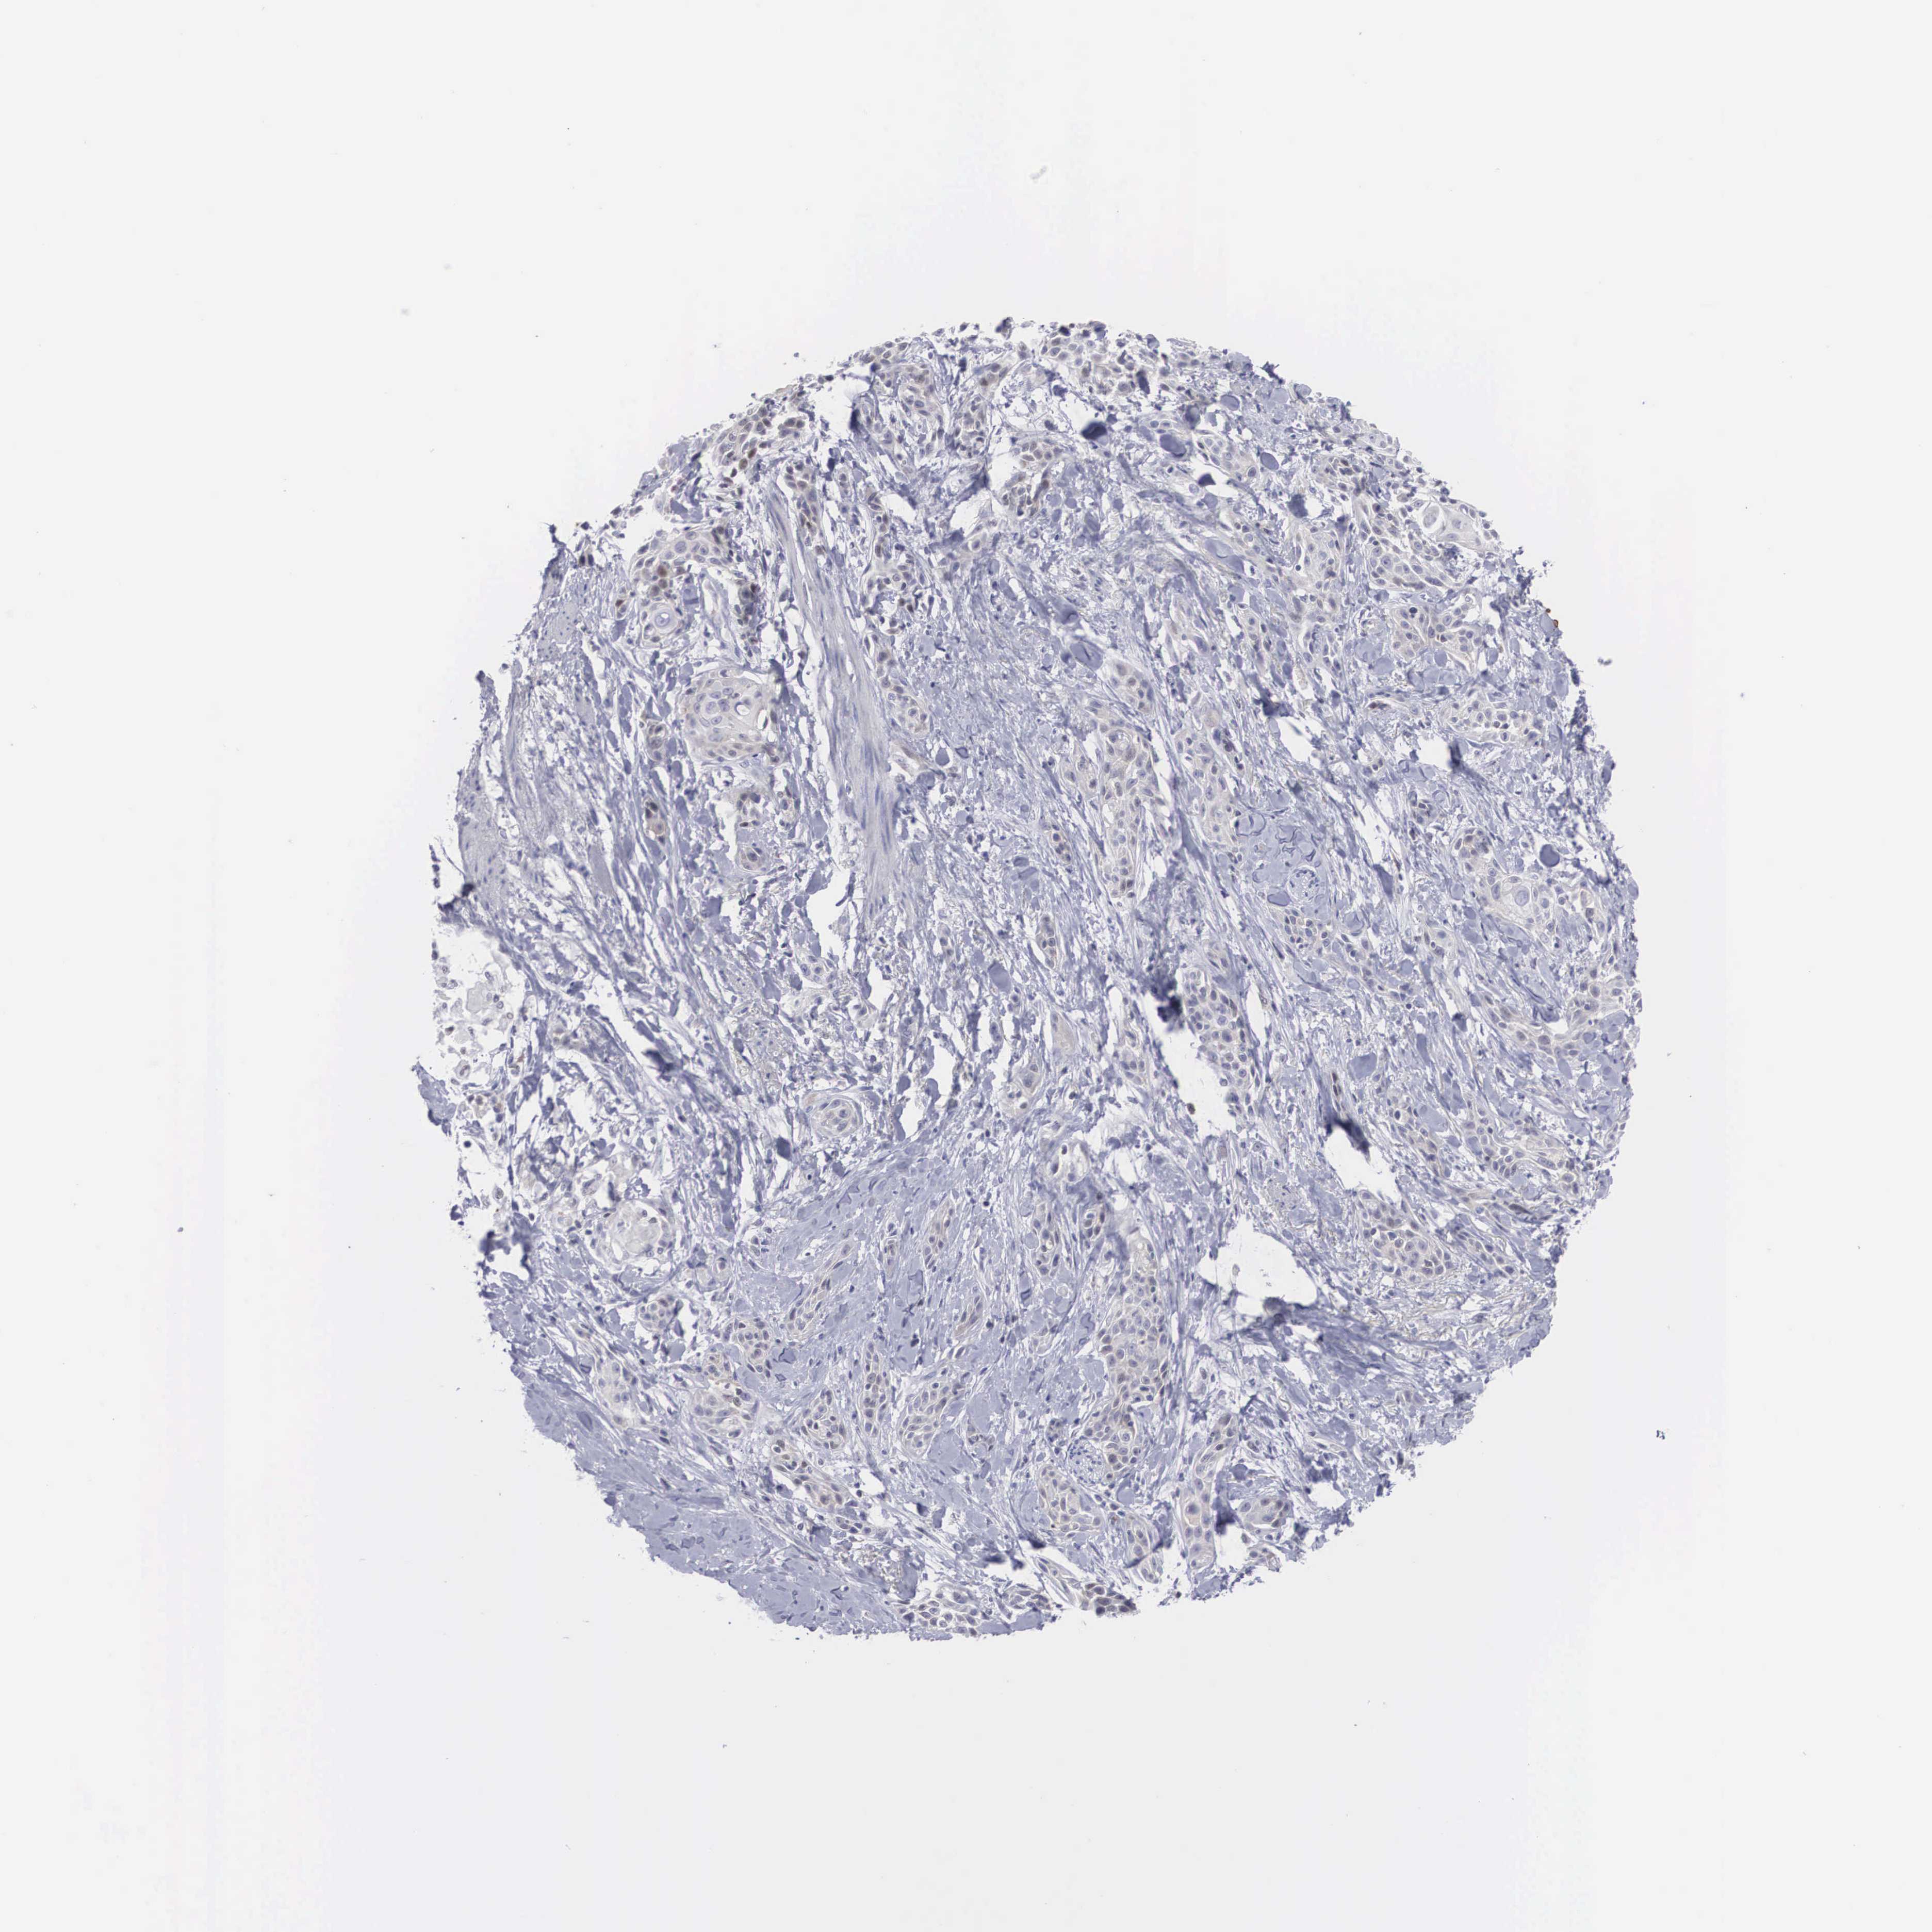

SKIN CANCER - Protein expressioni

A mouse-over function shows sample information and annotation data. Click on an image to view it in a full screen mode. Samples can be filtered based on level of antibody staining by selecting one or several of the following categories: high, medium, low and not detected. The assay and annotation is described here.

Antibody stainingi

Antibody staining in the annotated cell types in the current human tissue is reported as not detected, low, medium, or high, based on conventional immunohistochemistry profiling in selected tissues. This score is based on the combination of the staining intensity and fraction of stained cells.

Each image is clickable and will lead to virtual microscopy that enables deeper exploration of all samples and also displays staining intensity scores, fraction scores and subcellular localization as well as patient and tissue information for each sample.

Antibody HPA000251

Staining

High

Medium

Low

Not detected

Intensity

Strong

Moderate

Weak

Negative

Quantity

>75%

75%-25%

<25%

None

Location

Nuclear

Cytoplasmic/membranous

Cytoplasmic/membranous,nuclear

Basal cell carcinoma